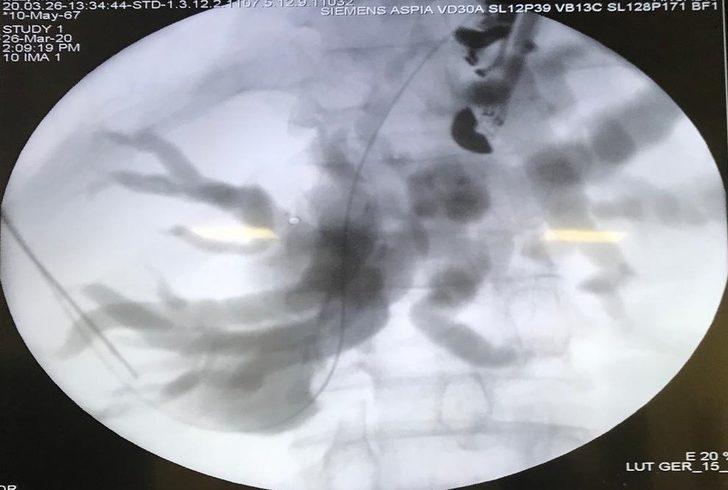

Mide kanseri nedeniyle midesi tamamen alınan ve yemek borusu ince barsaklarına bağlanan 54 yaşında erkek hasta, hastalığının nüks etmesi ve safra yollarını sıkıştırması nedeniyle sarılık ve kaşıntı şikayeti ile Düzce Üniversitesi Sağlık Uygulama ve Araştırma Merkezi’ne başvurdu. Midesinin tamamen alınmış olması sebebiyle konvansiyonel ERCP (Endoskopik Retrograd Kolanjiyo Pankreatografi) işlemine uygun olmayan hastanın, ciltten karaciğerinin iğne ile delinmesi ve bir torba vasıtasıyla safrasının dışarı alınması gerekiyordu. Ancak Düzce Üniversitesi Hastanesi’nde yapılan değerlendirme sonrası dünyada yeni bir yöntem olan Endoskopik Ultrasonografi ile hastanın ince barsaklarından karaciğerine bir iğne yardımı ile girilip, safranın karaciğerden ince barsağa bir stent vasıtasıyla akıtılabileceği belirlendi. İç Hastalıkları Anabilim Dalı ve Gastroenteroloji Bilim Dalı Öğretim Üyesi Doç. Dr. Serkan Torun ve Genel Cerrahi Anabilim Dalı’ndan Dr. Öğr. Üyesi Mehmet Fuat Çetin, hasta ve hasta yakınlarının ortak kararı ile 54 yaşındaki hastaya Hibrid EUS-ERCP işlemini başarıyla gerçekleştirdi. İşlem öncesi 29 olan sarılık değeri, 1 hafta sonra 5 seviyesine kadar gerileyen hasta taburcu edildi. Hastanın 2 hafta sonra yapılan poliklinik kontrolünde sarılık değerinin daha da gerilemiş olduğu görüldü. Doç. Dr. Torun ve Dr. Öğr. Üyesi Çetin konuya ilişkin yaptığı açıklamada “ Endoskopik Ultrasonografi kılavuzluğunda ERCP ya da Endoskopik Ultrasonografi kılavuzluğunda Biliyer Drenaj, EUS-BD, EURCP gibi isimlerle alınan ve nispeten tüm dünyada yeni olduğu için henüz adı bile netleşmemiş olan bu işlem, gelişmiş ülkelerde dahi sayılı merkezlerde yapılmakta olup, tam donanımlı ERCP ve Endoskopik Ultrasonografi ekipmanlarının varlığını gerektirmektedir.” dedi. Türkiye’de ilk kez bir devlet kurumunda midesi olmayan hastaya Hibrid EUS-ERCP yapıldığını vurgulayan öğretim Üyelerimiz, komplikasyon riskinin diğer işleme göre bir miktar daha fazla olmasına karşın bu işlem sonrası hastanın torba taşımasına gerek kalmadığını ifade etti.